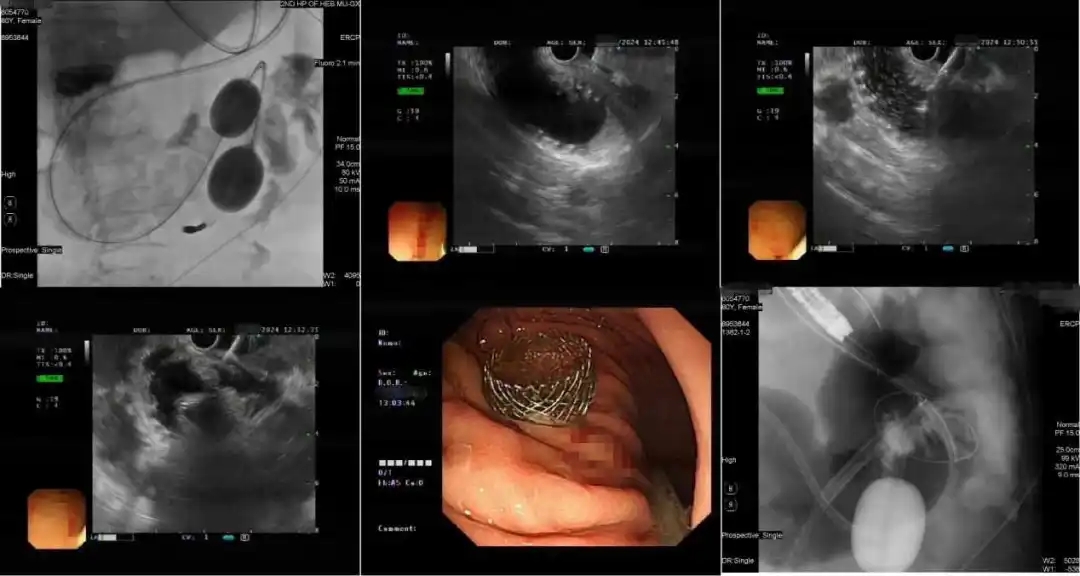

手术内镜图片

术中,该内镜团队凭借精湛技术、丰富经验,紧密协作、沉着冷静、有条不紊地展开手术,用时不到一个小时就顺利完成手术。术后胃腔造影显示:造影剂正常流入空肠。患者无不适,恢复良好,1天经口进流食,3天进半流食,顺利出院。